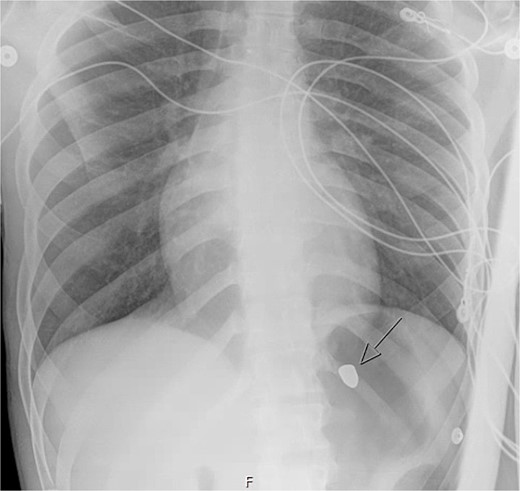

A 21-year-old male with a GSW to the left scapula presented to our Level 1 trauma center. He was stable but had flaccid paralysis and no rectal tone. A chest X-ray showed a bullet in the upper mediastinum (Fig. 1), prompting a computed tomography (CT) angiogram. The CT revealed a C6 cervical spine fracture, epidural hematoma, pneumomediastinum, and the bullet in the mediastinum at approximately the level of T3, but no hemorrhage (Fig. 2). Immediate upper endoscopy and bronchoscopy under general anesthesia were normal. He was extubated and monitored in the trauma ICU.